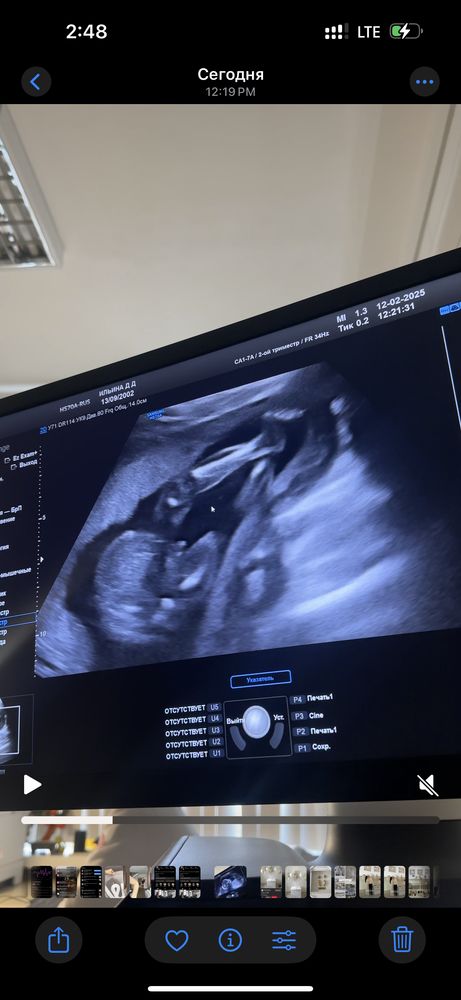

Пол малышаДобрый день, сделала второй скрининг, пол попросила не говорить, но когда засняла видео с узи начала его разглядывать дабы найти пол )))

Теперь не могу понять, мальчик это или пуповина

Бусинка, обычно просто пол смотрят снизу, а тут сбоку вид, у девочек вроде тоже выпирает бугорок 🙈

Ильина Дарья, да, выпирает, но не как у мальчиков, у девочек больше лежит этот бугорок, у мальчиков он как бы стоит )) вы потом как узнаете, отпишитесь) очень интересно, угадали ли мы )))

Ильина Дарья, кстати, на ваших неделях уже нет полового бугорка, уже полноценные гениталии. Мне на 15,6 на платном узи показали писюн и яички с разных сторон, и сбоку там уже полноценно все было, и снизу видно. 1 марта у меня 2 скрининг, вот хочу снова посмотреть, а то до всех пор не верится, вроде все видела сама своими глазами, и в тоже время переживания; а вдруг другой пол и неверно показали 😅😂 эх, беременные загоны